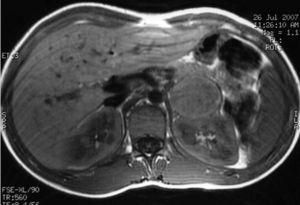

A los 40 años fue estudiada por dispepsia y diarreas, visualizándose en la ecografía abdominal un nódulo adrenal derecho. Refería sudoración e intolerancia al calor en los últimos 2 meses y la TA en consulta fue de 158/92mmHg. Analítica general sin alteraciones. Se solicitaron catecolaminas y metanefrinas urinarias con los siguientes resultados: adrenalina: 117mcg/24h (VN: 0,5-20mcg/24h), noradrenalina: 424mcg/24h (VN: 14-80mcg/24h), metanefrina: 1.386mcg/24h (VN: 86-320mcg/24h), y normetanefrina: 1.720mcg/24h (VN: 129-400mcg/24h). La TC abdominal confirmó un nódulo adrenal derecho de 3,5cm, homogéneo, de 44UH (fig. 1). La gammagrafía con meta-I-bencil-guanidina (MIBG) mostró captación en la suprarrenal derecha. Se intervino por vía laparoscópica tras alfa bloqueo farmacológico con 10mg/d de fenoxibenzamida. La anatomía patológica fue compatible con feocromocitoma encapsulado.